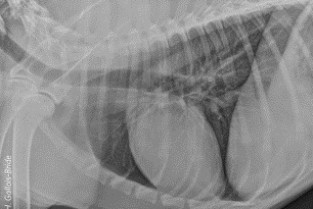

Le GEIM vous propose une séance de travaux pratiques de radiographies sur le thorax. Tous les aspects sont abordés sous la forme de TP de lecture de radiographies numériques sur station de travail Osirix sur Mac (3 vétérinaires maximum/ordinateur).

- adopter une méthodologie pour interpréter des radiographies thoraciques chez les carnivores domestiques ;

- décrire la radioanatomie du thorax chez les Carnivores domestiques.